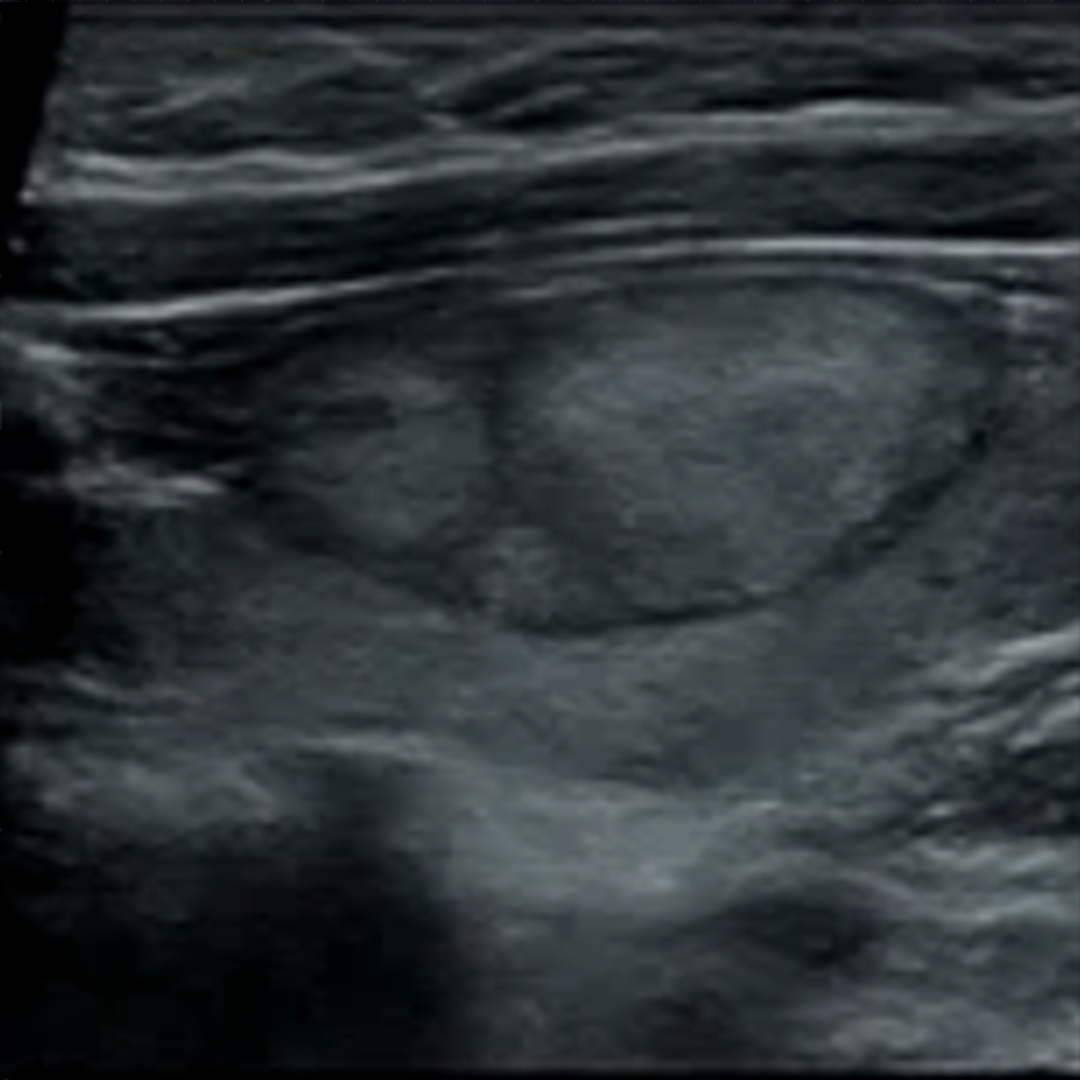

02、看边界

1. 清晰:结节与周围甲状腺组织界限清楚,提示趋向于良性结节可能性大。

2. 不清晰:结节与周围甲状腺组织界限不清,提示趋向于恶性肿瘤可能性大。

甲状腺结节超声图像

03、看形态

1. 形态规则:提示趋向于良性结节可能。

2. 形态不规则:提示趋向于恶性结节可能。甲状腺癌结节多具有“侵略性”的扩张性或侵润性生长,呈现为“张牙舞爪”的分叶状或成角畸形。

甲状腺结节测量